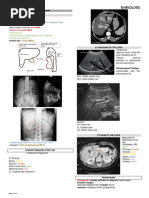

Flow through the Digestive System

You will need

to know the

order of flow

for food

moving

through the

digestive

system on

your next test.